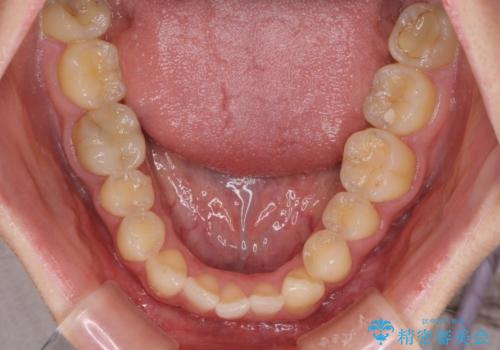

診査を行ったところ、下顎前歯が1本欠損しており、下顎歯列が上顎よりも小さくなっていることで、上顎にデコボコが生じていました。

口元を見ると抜歯をして突出感を改善するような状態ではなかったため、上顎歯列のデコボコを整えて、歯列全体を後方に移動させることでバランスを取ることとしました。